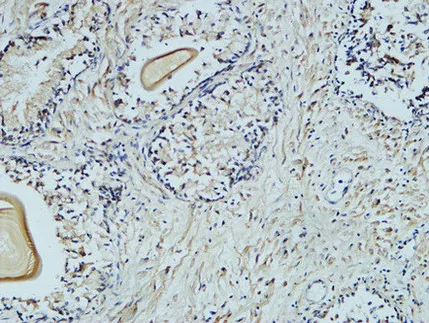

Bax(6F11)Mouse Monoclonal Antibody

Cat: AMM07478

Size1:50μL Price1:$118

Size2:100μL Price2:$220

Size3:200μL Price3:$380

Application:IF-P,IF-F,ICC/IF,WB,IHC-P

Reactivity:Human,Rat,Mouse,Chicken,Silkworm

Conjugate:Unconjugated

Optional conjugates: Biotin, FITC (free of charge). See other 26 conjugates.

Gene Name:BAX